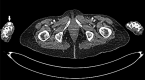

True aneurysms of hand arteries are rare. I present a case of a true saccular aneurysm of the distal radial artery in a 65-year-old woman with no history of trauma. The CT angiography, intraoperative features, operative procedure, histopathological examination and literature review are presented and discussed.